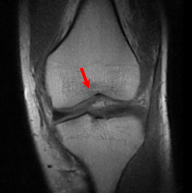

5.3 Out-of-Domain Generalisation

One way to test the generalization capability of the trained X-Diffusion is to test it on a completely different domain from an MRI dataset not seen during training. We report the single-slice results on NYU fastMRI [37, 82], a knee MRI dataset, using the X-Diffusion trained on the BRATS brain MRIs. The results are shown in Figure 9 and Table 2. It shows how successfully X-Diffusion is able to generate knee MRIs from a single image, despite not seeing knees at all in training. To qualitatively assess how realistic our generated 3D volumes were (produced from a single slice), we gave 20 generated examples alongside their real MRI counterparts to an expert orthopaedic surgeon. He was then asked to identify the real example from a given pair. The surgeon identified with certainty only 10 real knee MRIs out of 17, while could not decide on the remaining 3 of the 20 MRI pairs. This further validates the generated out-of-domain MRIs.